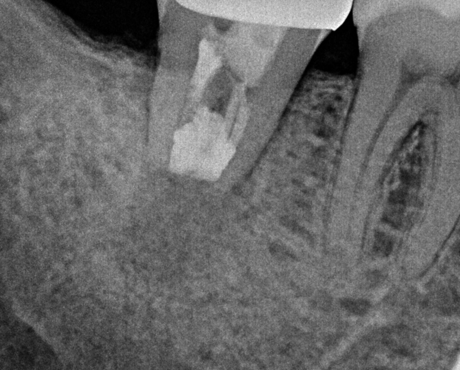

치료 직후

치료 1년 반 후